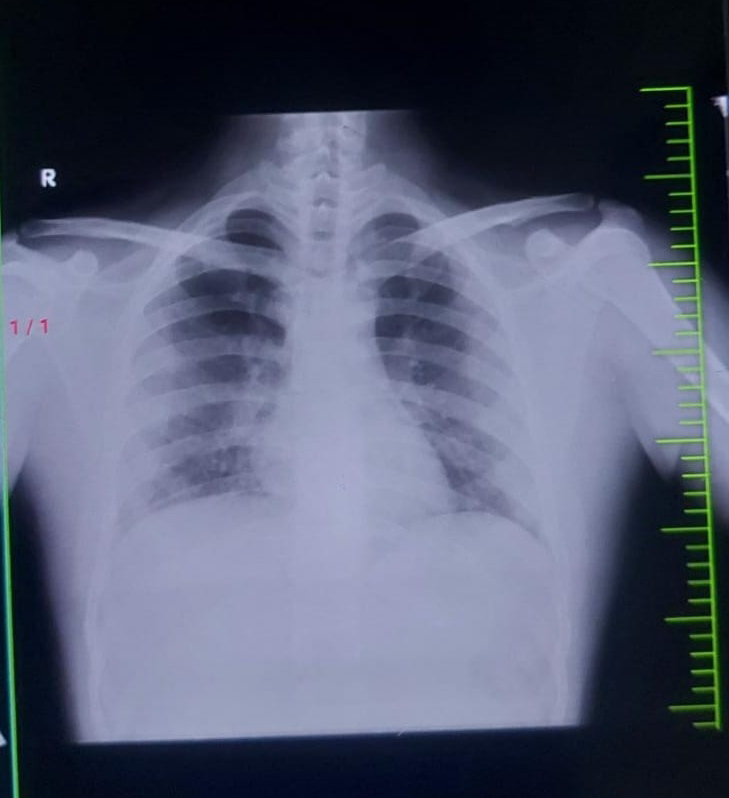

Respiratory system examination :

Inspection -

Chest appears to be bilaterally symmetrical , elliptical in shape

Trachea appears to be central [ midline ] in position

Chest in moving equal and normal with respiration

No sinus , no scars , no dilated veins , no swellings , no drooping of shoulder , no hallowing

Palpation -

All inspectory findings are confirmed

No local rise of temperature , no tenderness

Trachea -midline

Apical impulse is felt

Tactile focal fermitus - appreciated

No palpable swellings , no crowding of ribs

Percussion -

Auscultation - bilateral normal vesicular breath sounds are heard